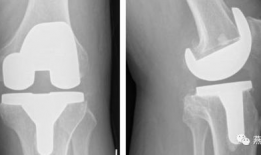

你有没有想过,当你的膝关节像老化的弹簧一样“嘎吱嘎吱”作响时,会有一种神奇的手术能把它换成一个全新的呢?没错,就是膝关节置换手术...